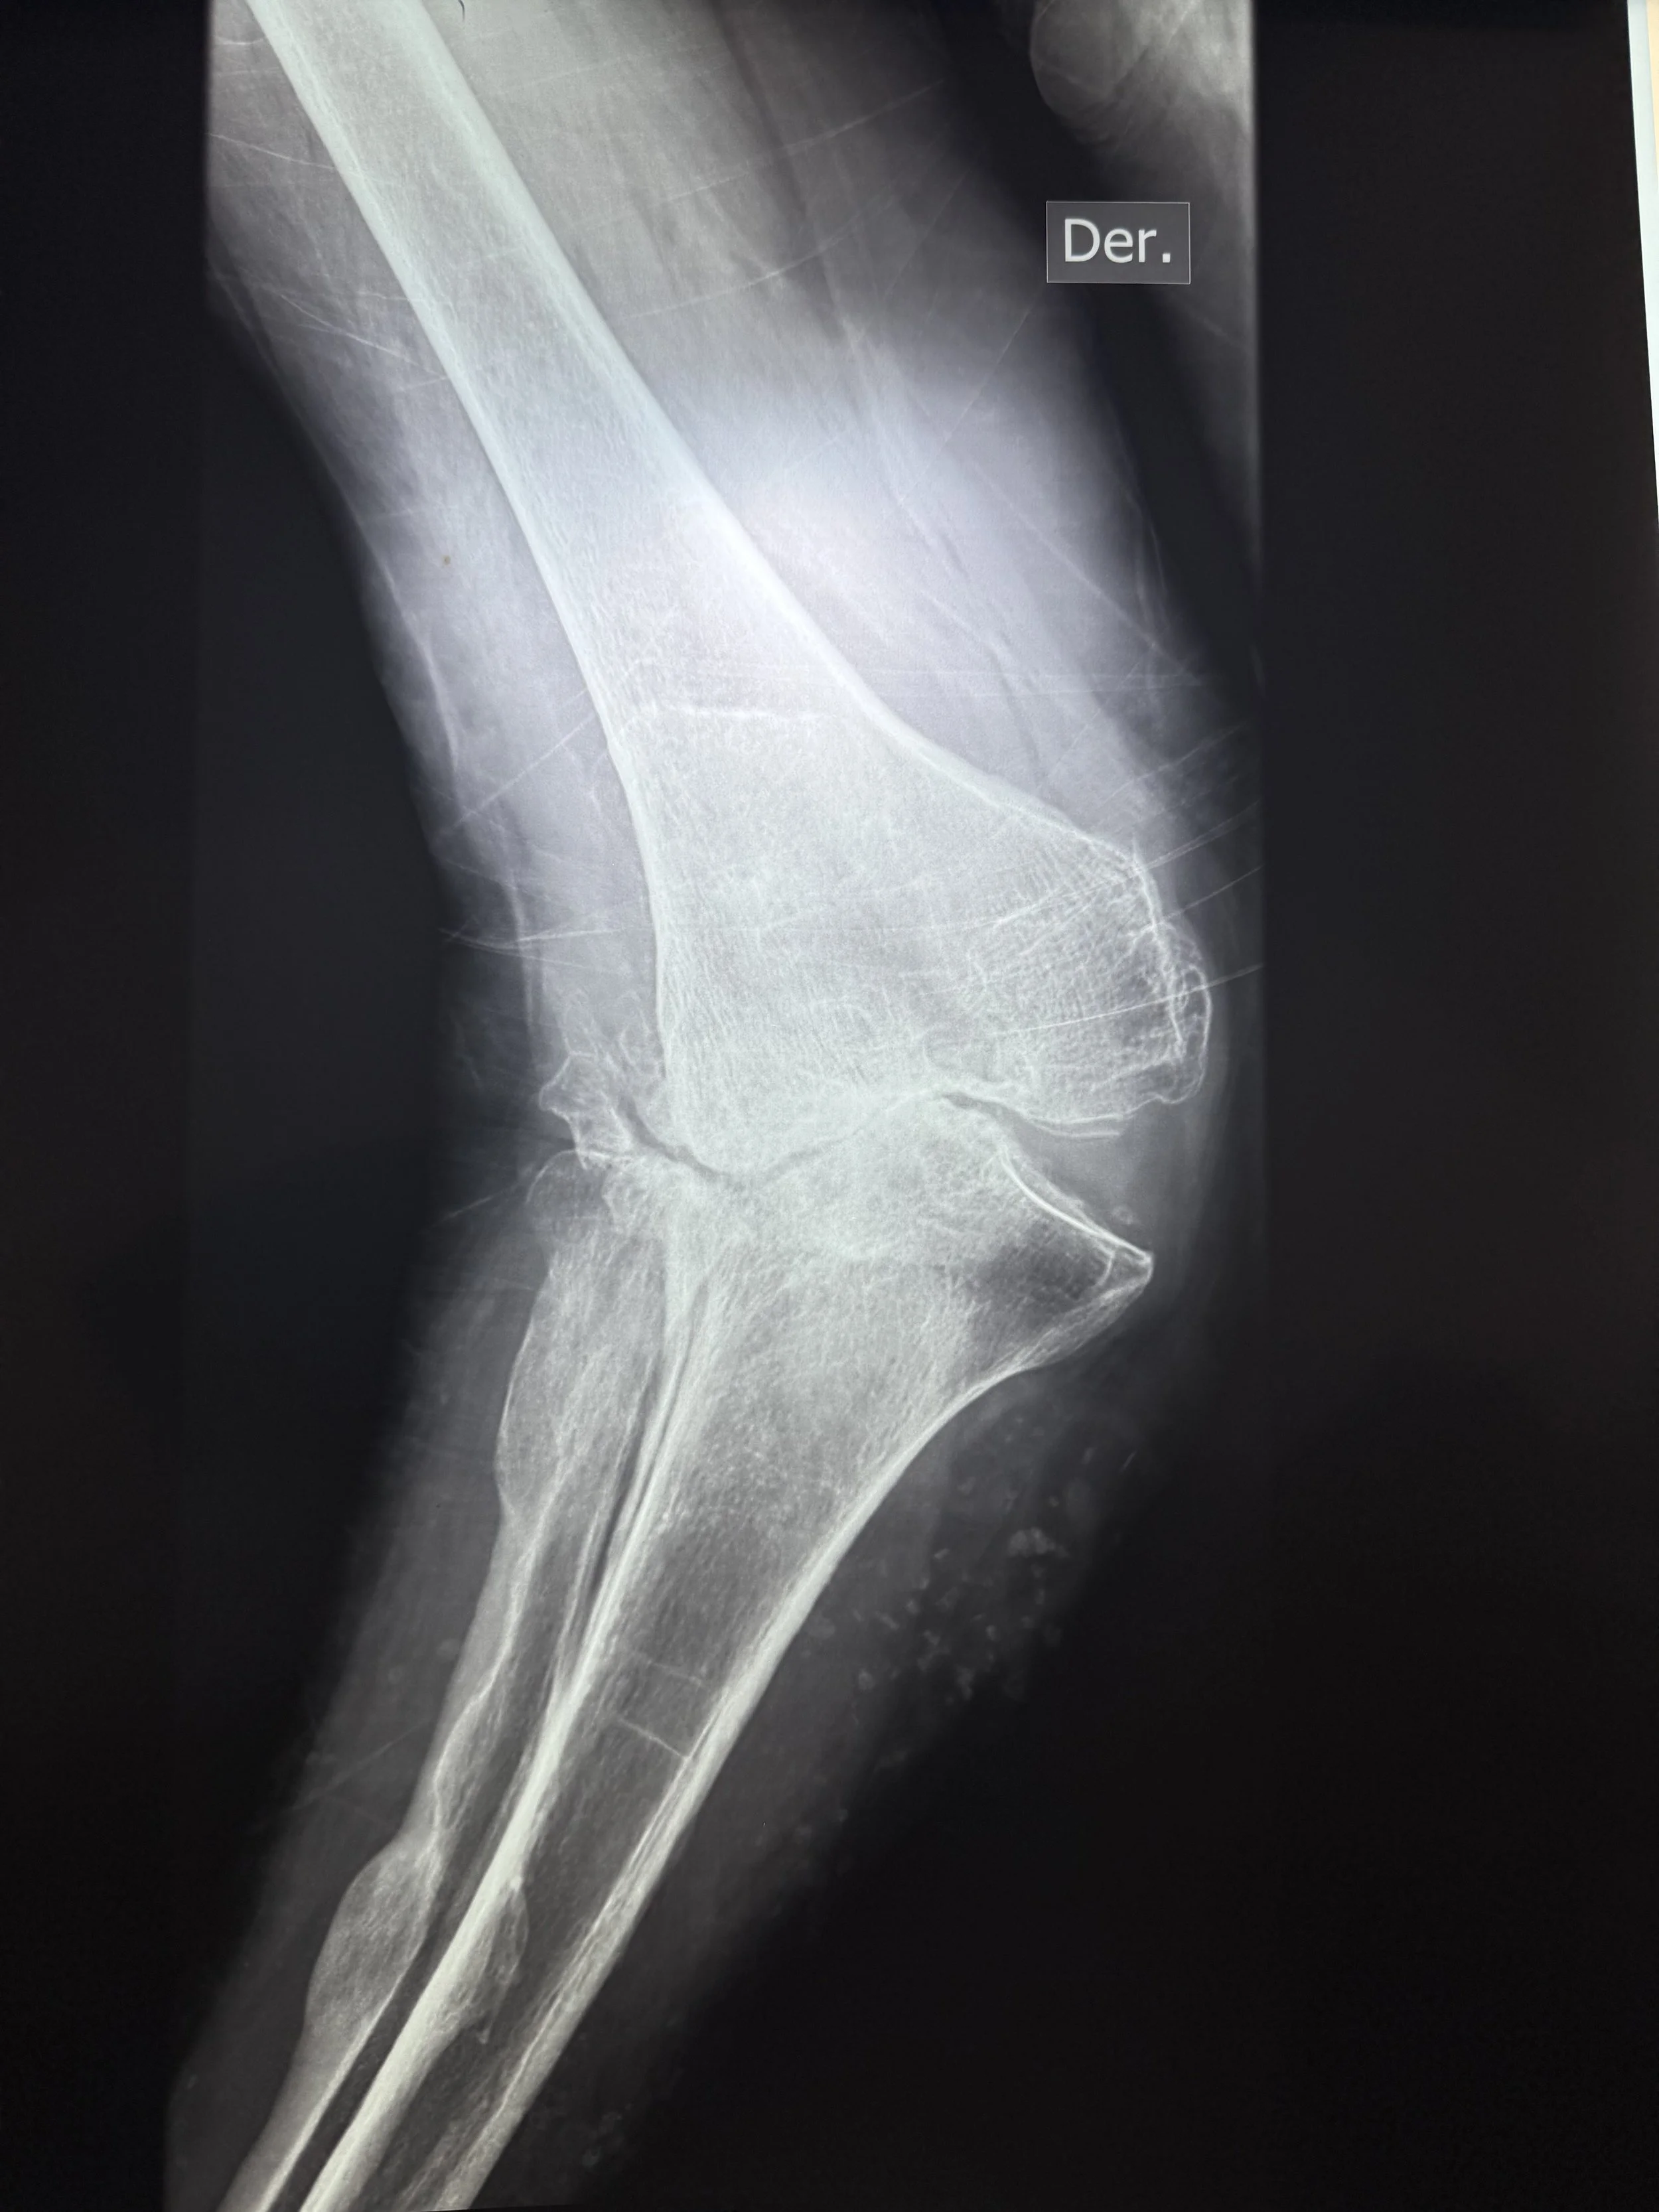

Today, we had the humble privilege of seeing over 100 patients in need of surgical care for hip, knee, foot, and ankle deformity. We will begin tomorrow with 6 operating rooms, 25 cases planned, 9 surgeons, 7 anesthesiologists, and 43 health care professionals working together.